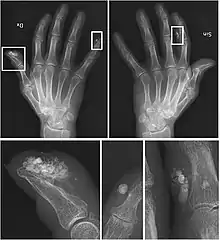

También se deben hacer pruebas de imagen como radiografías y TAC (tomografía axial computarizada) en las que se puedan objetivar las calcificaciones.